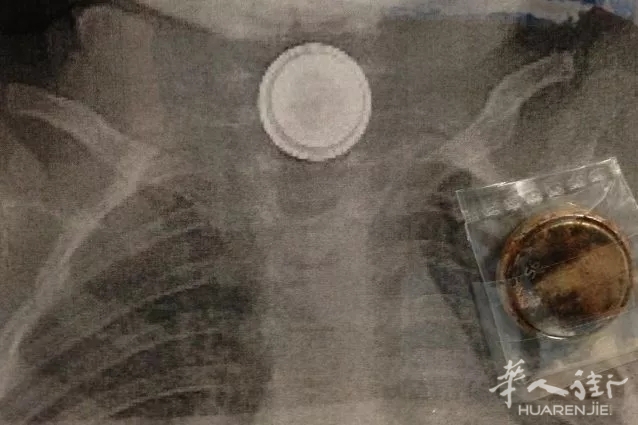

意大利Roma.fanpage网站8月2日报道,近日,罗马一名4岁儿童因突发腹痛被父母送到Bambino Gesù儿童医院。医务人员通过X光片发现小孩的食道里有一枚纽扣电池,而这枚电池在孩子体内已存在多日。电池释放的电荷灼伤了孩子的体内组织,并危及生命。